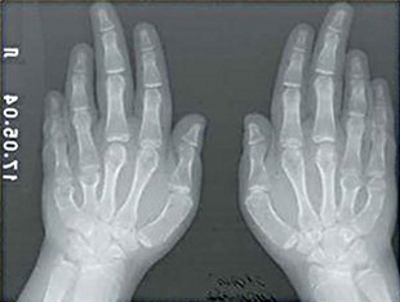

При брахидактилии наблюдается укорочение пальцев на обеих конечностях, иногда с их сплющенной формой или расщеплением. Часто также можно заметить отклонения в размерах или полное отсутствие ногтевых пластин.

На изображении представлен пример брахидактилии.